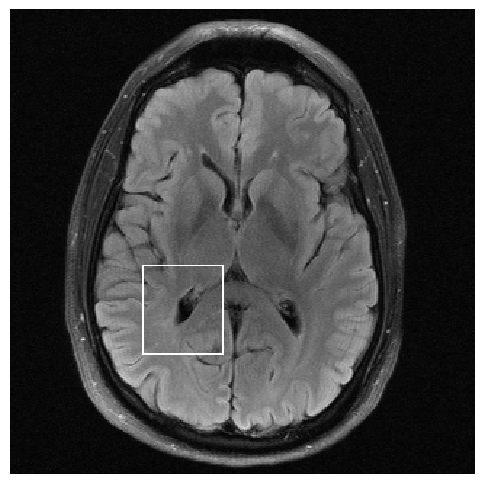

Figure 3: Reconstructions results. Rows 1 and 3: Examples of comparing the ground truth (GT) fully sampled image to the reconstructed images obtained by the three models (1-3), NPB-REC, baseline, E2E-VarNet trained with Dropout, and the NPB-REC std. map at accelerations R=4𝑅4R=4italic_R = 4, R=8𝑅8R=8italic_R = 8, respectively. Rows 2 and 4: The corresponding annotated ROIS of Nonspecific white matter lesions.

Fig. 3 presents examples of reconstruction results obtained by (1) our NPB-REC approach, (2) the baseline, and (3) Monte Carlo Dropout, for equispaced masks with two different acceleration rates R=4𝑅4R=4italic_R = 4 and R=8𝑅8R=8italic_R = 8. The reconstructed images predicted by the three models are smoother than the reference image. This is due to the fact that all the models were trained with SSIM loss, which tends to produce overly smooth reconstructions while preserving the diagnostic content and the anatomical features Sriram et al. (2020a). These images can be enhanced by dithering the image by adding a small amount of random Gaussian noise to produce a more textured reconstruction, as proposed in Sriram et al. (2020b).

Table 1 presents the mean PSNR and SSIM metrics, calculated over the whole inference set, for the three models. Our NPB-REC approach achieved significant improvements over the other methods in terms of PSNR and SSIM (Wilcoxon signed-rank test, pmuch-less-than\ll1e-4, except for SSIM values in line W, R=4𝑅4R=4italic_R = 4 where they are roughly the same for NPB-REC and Baseline). The improvement in the reconstruction performance can be noted both quantitatively from the metrics, especially for masks with acceleration rate R=8𝑅8R=8italic_R = 8, and qualitatively via the images of annotations, where our results show less smoothness than those obtained by Dropout.